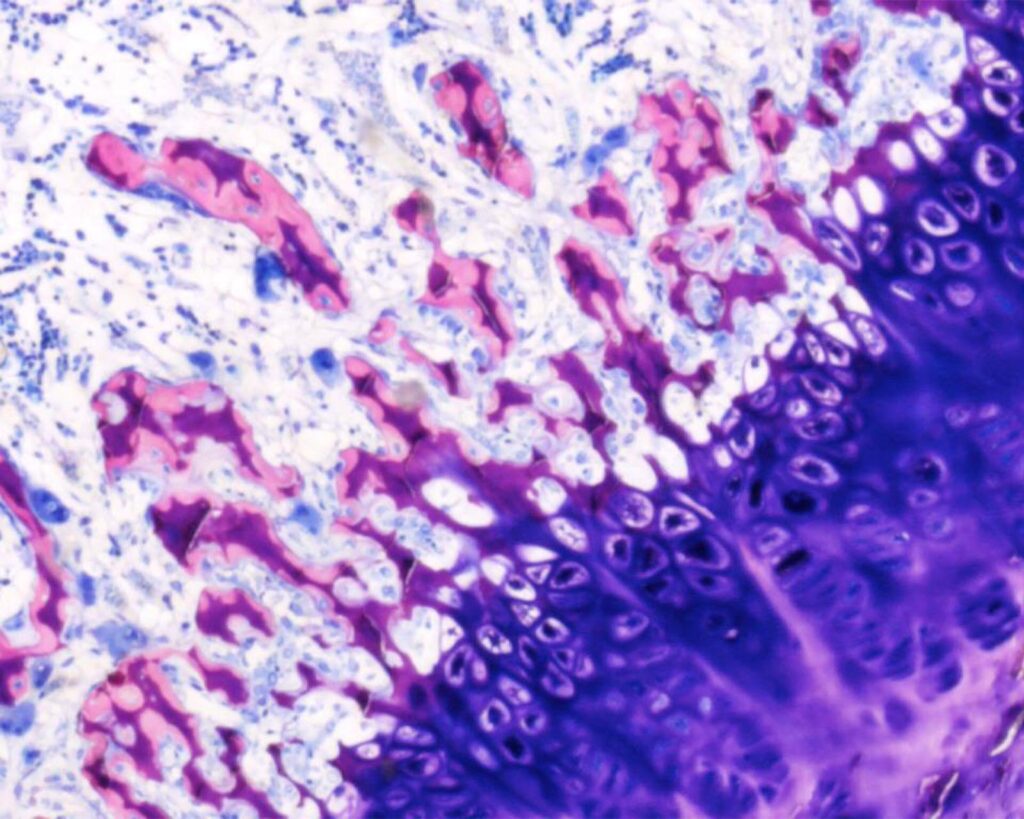

Preclinical Research

Pharmaceutical, biotechnology and medical device companies look to Biograding Solutions Pharmaceutical, biotechnology and medical device companies look to Biograding Solutions for a complete range of customised programs in bone, cartilage, spine, inflammation and pain therapeutic areas.

Preclinical Histology Slides Performed